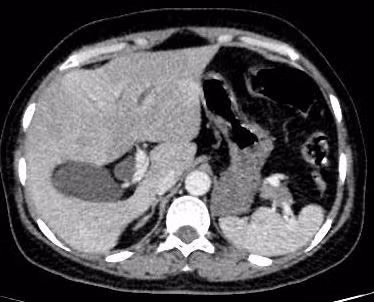

Sau can thiệp ERCP, các bác sĩ gắp được 3 con sán lá gan nhỏ còn sống (dài 10-15 mm, ngang 3-4 mm) ra khỏi cơ thể bệnh nhân.

Bệnh nhân tiếp tục dùng thuốc điều trị đặc hiệu để diệt trứng sán còn tiềm ẩn trong người. Sau nội soi can thiệp, bệnh nhân hồi phục, tỉnh táo, hết nôn, hết đau và đã được xuất viện.